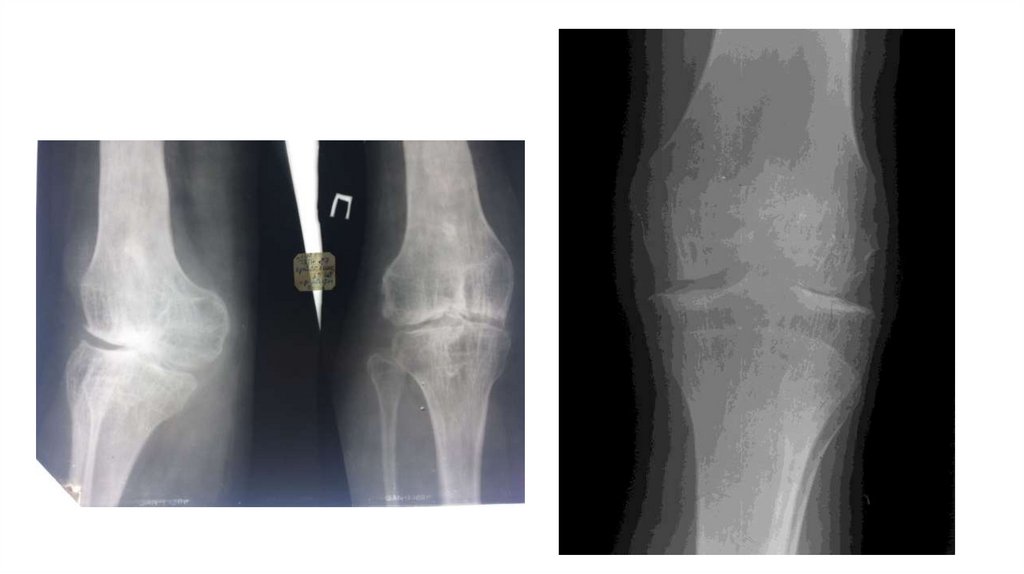

«Воспалительные

заболевания опорнодвигательного аппарата»